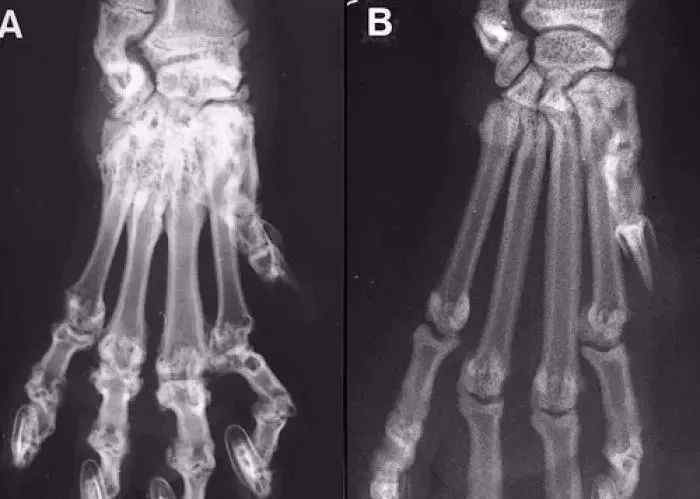

患病的折耳猫拍了x光片,骨头已经变形。

不要以为折耳猫的肉垫很厚很可爱,因为是骨头不正常造成的。